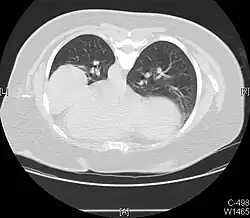

A pleural effusion is an accumulation of fluid inside the pleural space. If this collection of fluid gets large enough, it can also push structures in the chest away from it and cause a mediastinal shift. However, a pleural effusion can also pull the mediastinal structure towards itself. If this is the case, then there is an underlying condition causing the collapse of the lung on that side. An example is a tumor obstructing a bronchus and causing lung collapse and pleural effusion.[3]